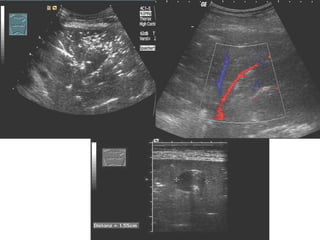

IVC Sonography

PROCEDURE

Probe Selection

1 Low frequency 2-5 MHz

2 Curvalinear probe

Where to put the probe…

 Probe position

 Subxiphoid

 Orientate probe in

longitudinal plane with

probe indicator to

patient’s head

 Slightly to right of

midline

IVC Longitudinal

Approach #2 – Anterior -Mid-Axillary

View

Landmarks

Aproach #2 – Anterior Mid-Axillary View

1 Place probe longitudinally in right anterior

mid-axillary line with marker towards the head

2 Look for IVC running longitudinally

adjacent to liver crossing the diaphragm.

3 Track superiorly until it enters right atrium

confirming that it is the IVC and not the aorta.

Measuring the IVC Diameter

Measure IVC 2cm

Inspiratory (Minimal) IVC

Diameter

Maximum (Expiratory) IVC

M-Mode IVC Diameters

CAVAL INDEX (CI)

CI =

minimal (inspiratory)

maximum (expiratory)

Volume

Depletion

Overload

0% 100%

IVC v CVP

Correlation Between IVC Diameter Plus CI and

CVP

IVC Max Diameter

(cm)

CI CVP

(mmHg)

< 1.5

100%

(total collapse)

0-5

1.5-2.5 > 50% 6-10

1.5-2.5 < 50% 11-15

> 2.5 < 50% 16-20

> 2.5

0%

(no collapse)

>20